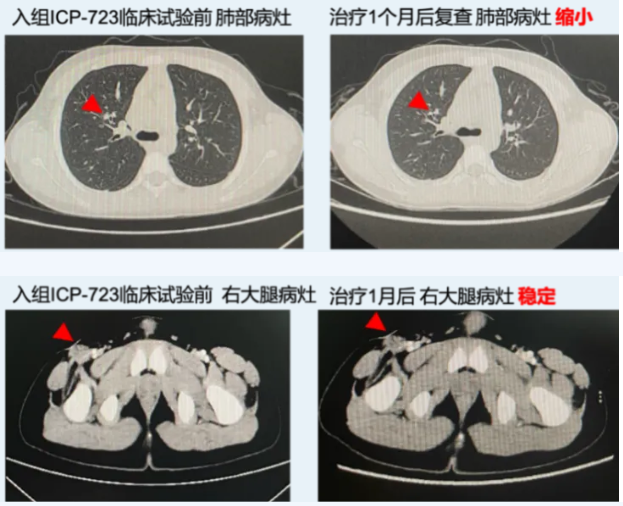

1代NTRK抑制剂耐药,ICP-723治疗后肿瘤显著缩小

一位软组织恶性梭形细胞肿瘤伴肺部转移的患者,基因检测显示ETV6-NTRK3融合,接受化疗和9个周期的第一代TRK抑制剂后出现疾病进展。在国内接受5个周期ICP-723的治疗后,肺部非靶病灶明显缩小、右大腿靶病灶达到手术条件,右大腿病灶手术切除后病理提示已未见肿瘤组织。